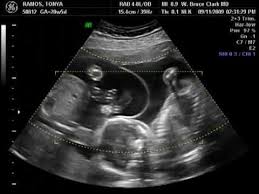

Detecting early fetal movement can also be felt in the second trimester by expecting moms usually around the 18th week. By 18 to 20 weeks a technician may be able to identify the babies sex assuming that both are positioned such that the technician can get a good look at their genitals. The following symptoms are commonly reported as signs that you may be pregnant with twins from the earliest weeks of pregnancy. It usually doubles every two to three days peaking at about eight to 11 weeks into the pregnancy.

An ultrasound scan is the only way to confirm that you re pregnant with twins mcaslan fraser nd nice 2011. After week 6 0 both hearts should be beating. As the babies grow there tends to be more movement and light flutters felt in the abdomen by the pregnant woman. Regardless elevated beta hcg levels in early pregnancy isn t a proper way to detect twins.

The earliest you re likely to find out is between 10 weeks and 14 weeks when you have your dating scan mcaslan fraser nd nhs 2019 nice 2011. If they are mo di or mo mo twins you have to wait until 6 full weeks have passed. All fraternal twins and 20 to 30 percent of identical twins have separate placentas. Generally when you are pregnant with twins fetal movements become more noticeable at weeks 18 through 20 of pregnancy and the same is true in singleton pregnancies al khan says.